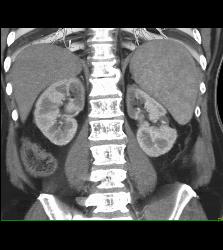

Acute Pyelonephritis